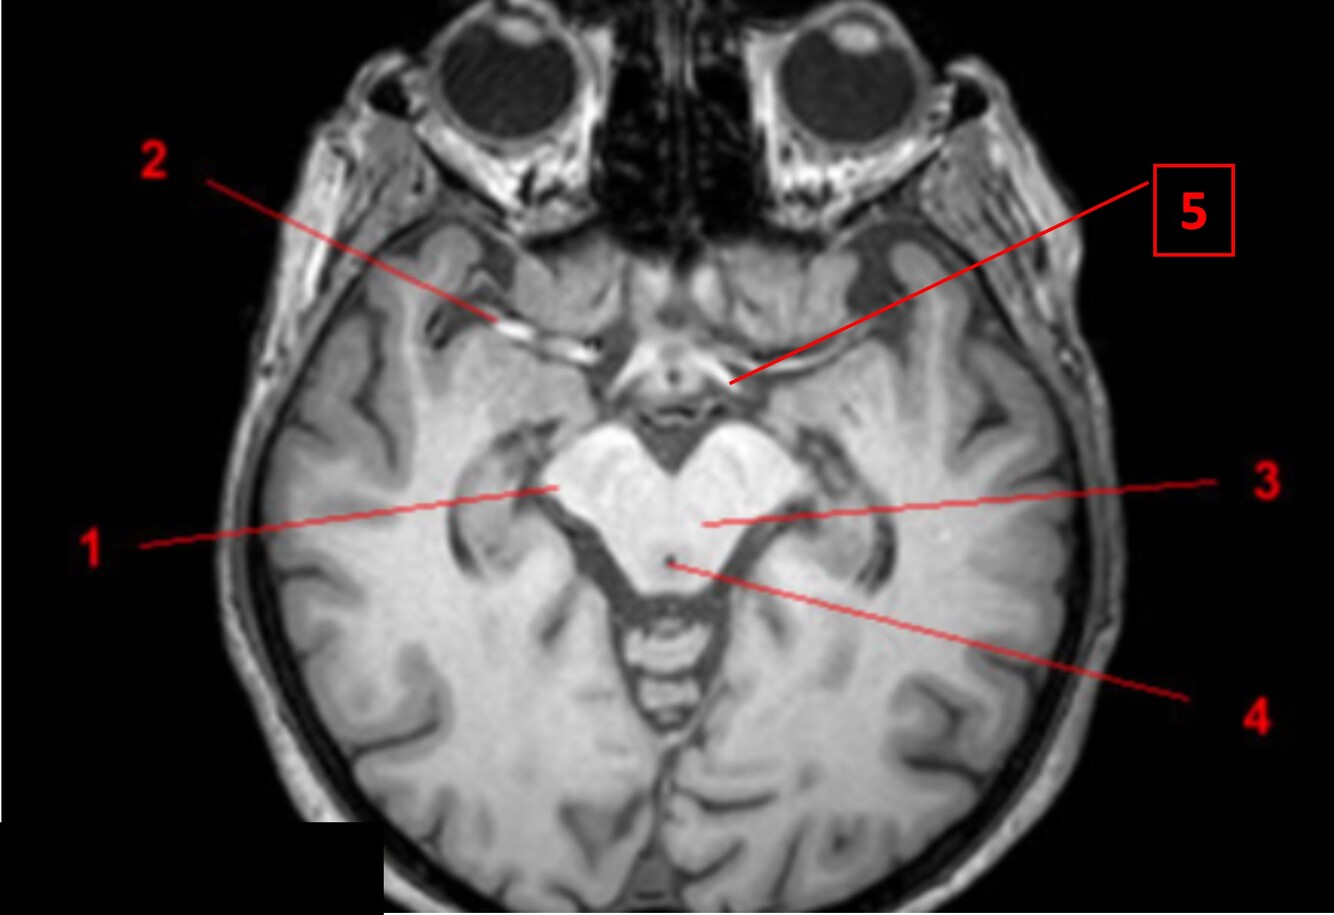

Label 1-3

1-Lt Optic nerve

2-Optic chiasm

3-Rt Optic tract

Label 1,10,12

1=Lt cerebral peduncle (midbrain)

10=Interpeduncular cistern

12=Cerebral aqueduct

Label 7-11

7=Rt Internal carotid artery

8=Optic chiasm

9=Pituitary gland

10-Lt lateral ventricle

11=Lt Cavernous sinus

Label a-e

a=Septum pellucidum

b=3rd ventricle

c=Lt Thalamus

d=Genu of corpus callosum

e=Splenium of corpus callosum